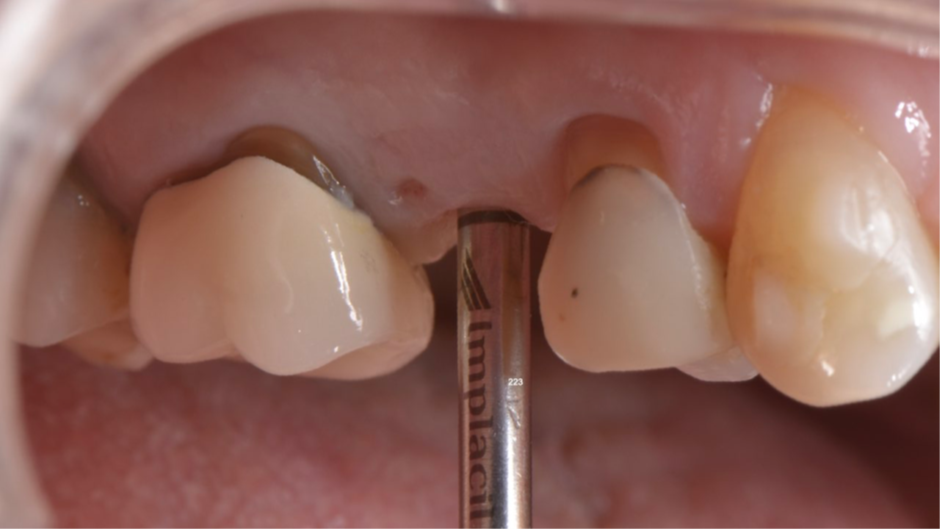

Para fazermos a coroa definitiva, precisamos posicionar a margem gengival semelhante aos dentes adjacentes. Nesse caso, usamos o túnel check de prótese CM para escolha da cinta do pilar (Figura 7). Temos que tomar muito cuidado em saber onde posicionar a margem gengival vestibular da coroa sobre implante, pois quando temos muita espessura de mucosa, a marcação do túnel check pode “confundir” no momento da seleção da cinta do pilar (Figura 8). O pilar de escolha para esse caso foi o Ideale 3.3×4 e foi planejado para ser instalado como uma cinta de 2,5mm, a fim de que a margem da coroa sobre implante fique semelhante à margem dos dentes adjacentes. Então, o pilar Ideale reto 3.3×4 com a cinta de 2,5mm foi instalado (Figura 9) para ser usado como pilar definitivo e fazer uma coroa provisória sobre o implante. A diferença de tamanho entre o diâmetro cervical do dente natural e o encaixe do implante pode resultar em um perfil inadequado da coroa. Se o perfil for subcontornado, não haverá pressão contralateral ou suporte para a mucosa, e as partículas de alimentos podem ficar retidas.

Figura 7 – Túnel check de prótese CM para escolha da cinta do pilar com muita espessura da mucosa.

Figura 8 – Túnel check de prótese CM com as marcações.

Figura 9 – Pilar Ideale reto 3.3×4 com a cinta de 2,5mm instalado.